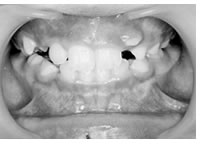

前歯部分の凸凹は上下とも重度であった。乳歯の虫歯も多く、歯磨き練習も重要でした。

右上の2番を1本だけ抜歯しました